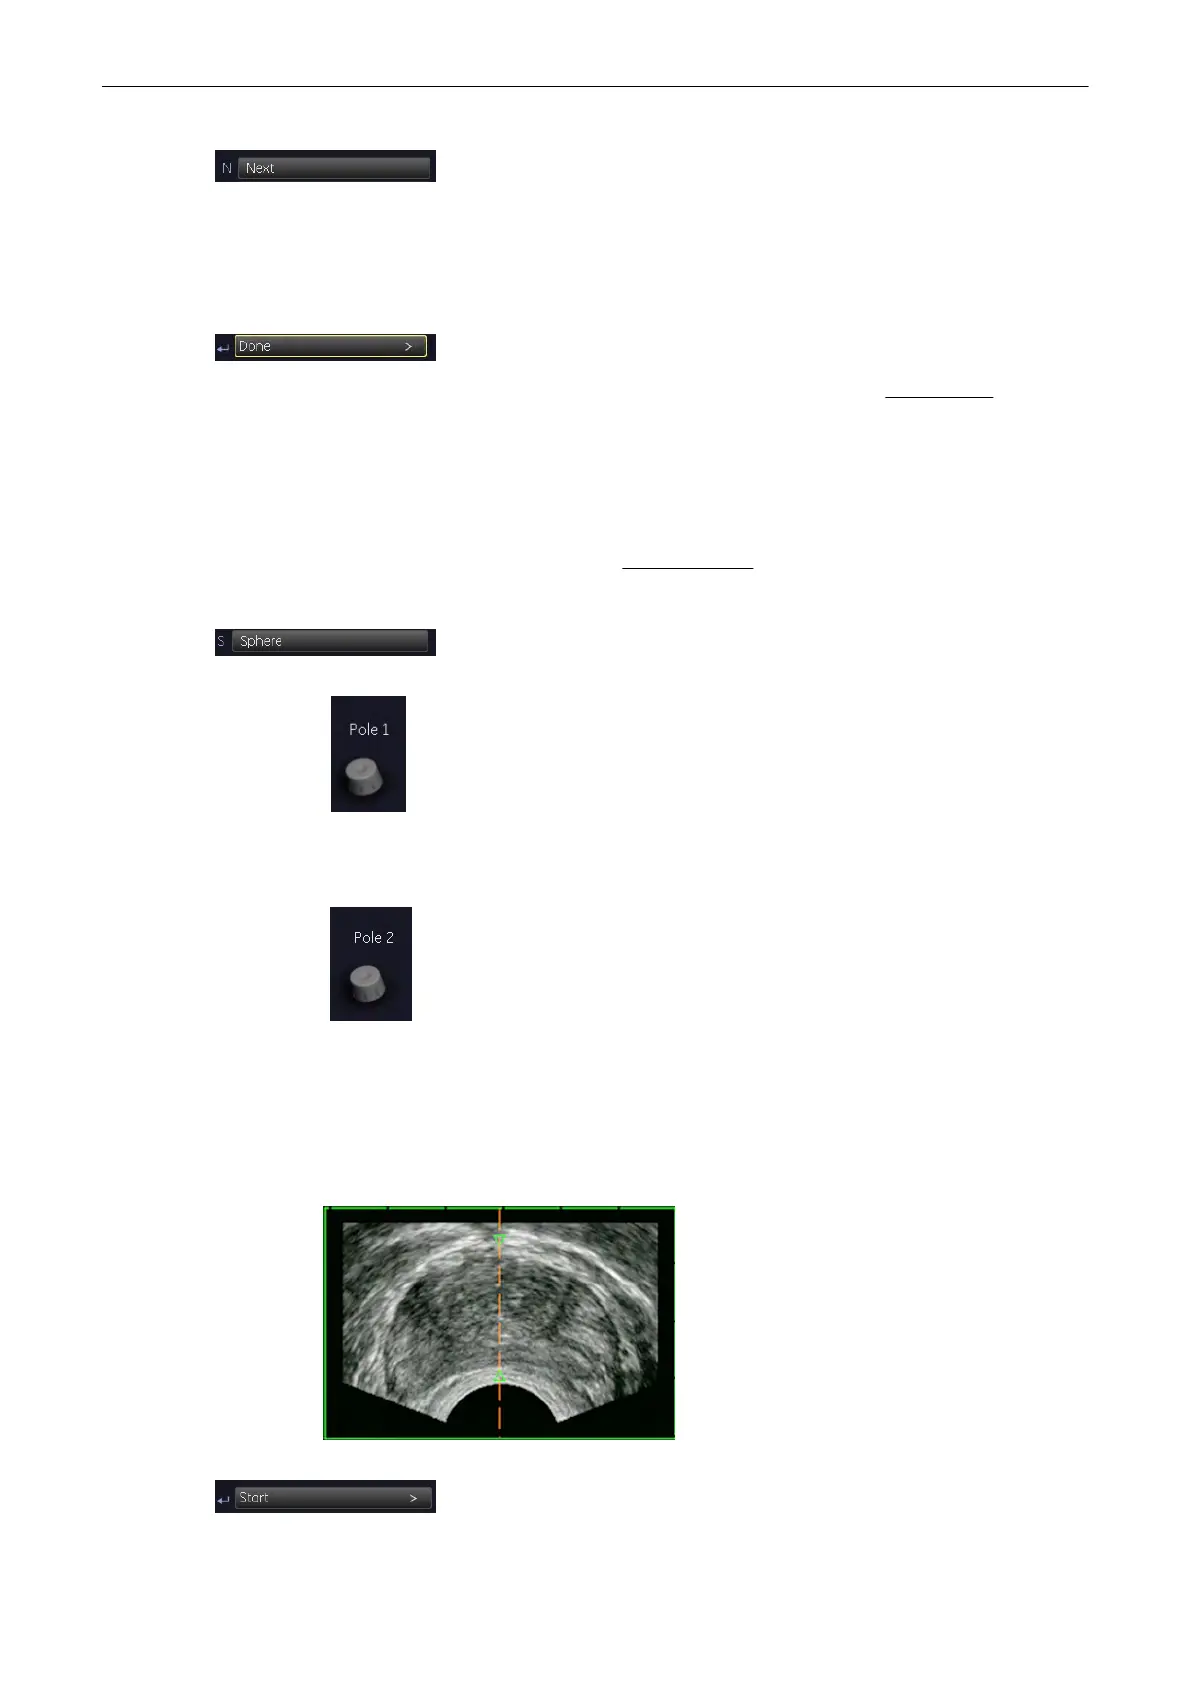

9.12.4.2 Automatic - Sphere

This computer assisted contour mode function is only useful if you want to outline the surface

of a sphere. Using this function a sphere round the main contour axis is generated within the

two green arrows. For details review:

1. In the “VOCAL Modes” menu, select the [Sphere] contour mode key.

Adjust the upper contour point (characterized by a green arrow) by using this control below the

menu area.

Adjust the lower contour point (characterized by a green arrow) by using this control below the

Two contour points are marked in the image plane(s) along the main contour axis to define the

poles of the (shell) contour. (All generated contours in the image planes cross the main

contour axis at these two points.)

4. To start defining the contour, select the [Start] key. The result is displayed

on the monitor.